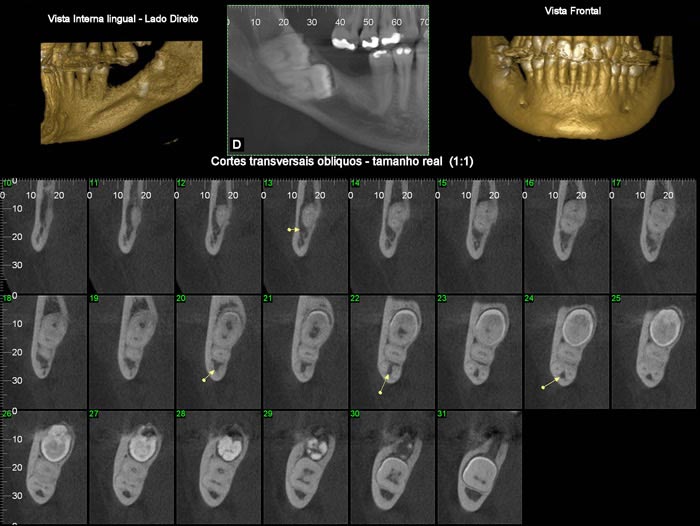

Nos softwares há ferramentas que permitem a reconstrução e a obtenção de novos cortes que mostram imagens de uso pontual na odontologia como os cortes transversais e longitudinais.

Os cortes transversais são cortes perpendiculares ao arco da maxila e mandíbula.

Na reconstrução panorâmica aparece uma régua no limite inferior que serve de localização para os cortes transversais.

Os cortes longitudinais são cortes no sentido vestíbulo lingual ou palatino, perpendiculares a uma reta traçada sobre o dente ou a área em questão.